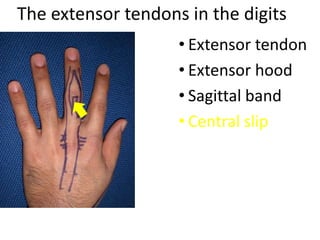

- It describes flexor tendon zones, extensor compartments, and pulley system anatomy.